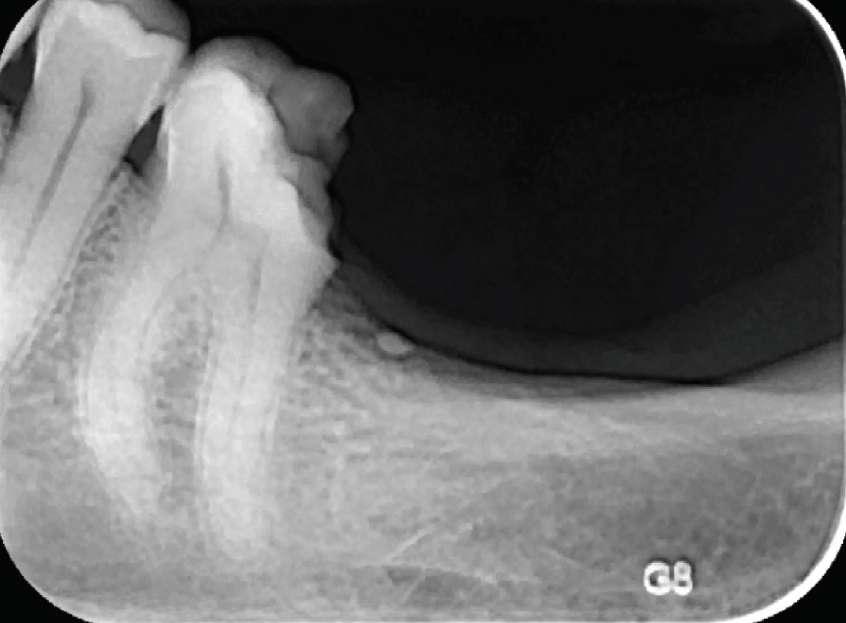

Die Patientin wurde zur Beurteilung und Behandlung von Zahn 36 an unsere endodontische Praxis überwiesen. Klinisch wies Nr. 36 eine MODKompositrestauration, eine negative Reaktion auf Kälte und eine Empfindlichkeit gegenüber Perkussion auf. Die präoperative Röntgenaufnahme ergab, dass Nr. 36 eine kleine periapikale Radioluzenz an der mesialen Wurzel und eine mittelgroße an der distalen Wurzel hatte.

Vor der Operation

Nach der Obturation Abschluss

Die Arbeitslängen wurden mit dem Apex-Locator bestimmt, gefolgt von einer röntgenologischen Bestätigung. Das Kanalsystem wurde mit BUSA BC Sealer und BC GP Point verschlossen.

Der Zugang wurde sofort mit einem faserverstärkten DualCure-Kernmaterial wiederhergestellt.